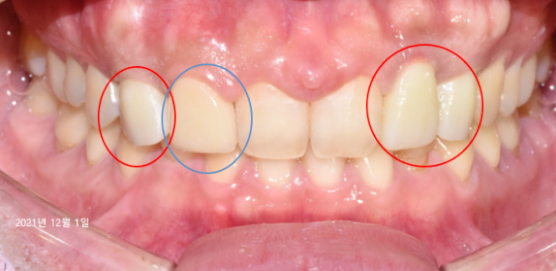

21.12.01

3개월 후 내원하셔서 임플란트 치료가 전부 완료된 사진입니다.

빨간색 동그라미 부분을 보시면 마지막 보철물까지 씌운 모습을 확인해 보실 수 있는데요.

파란색 동그라미 부분에 자리 잡고 있던 송곳니도 라미네이트를 통해 주변 치아와 조화롭게 자리하고 있습니다.